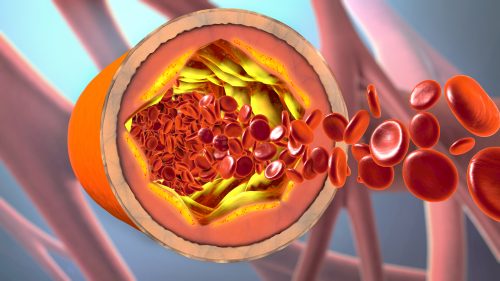

In the BASKET-SMALL 2 randomized controlled trial, researchers compared the effect of a drug-coated balloon (DCB) ...

Deep learning may be able to predict incomplete stent expansion, new research in JACC: Cardiovascular Interventions ...

Deep learning may be able to predict incomplete stent expansion, new research in JACC: Cardiovascular Interventions ...

A novel NanoCoated Coronary Stent (NCS) failed to meet noninferiority criteria to a drug eluting stent, new trial ...

Discontinuation of aspirin at 90 days following stenting and continuing on P2Y12 inhibitor monotherapy, was not ...

The Absorb bioresorbable vascular scaffold was shown to be noninferior to the Xience Cobalt ...

A novel polymer-free amphilimus-eluting stent was found to be safe and efficacious compared to the latest-generation ...

A polymer-coated zotarolimus-eluting stent (Resolute Onyx) with a novel thin-strut metallic platform demonstrated ...

Ultra-thin strut drug-eluting stents (DES) may promote better clinical outcomes than thicker strut second-generation DES ...